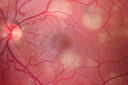

Birdshot Chorioretinitis Mild - Asymptomatic934 views59-year-old man has birdshot chorioretinopathy in both eyes. Vision OD 20/25, OS 20/20. IOP: OD 16, OS 14. The right eye has a posterior chamber intraocular lens in good position. There is 1+ posterior capsular opacity. The left eye has 2+ nuclear sclerosis.

EXTENDED OPHTHALMOSCOPY:

OD: Vertical C/D ration is 0.8. There is patchy depigmented lesion in the nasal periphery. The retina is attached with peripheral laser.

OS: Vertical C/D ratio is 0.4. There are peripheral punched out lesions in the periphery